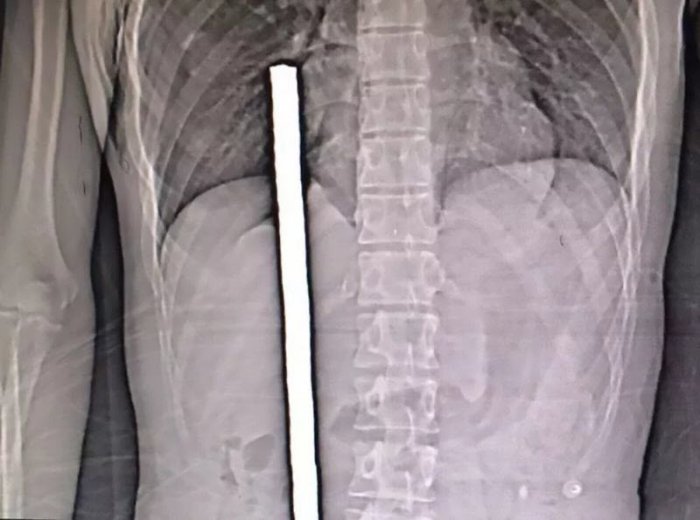

22-летний китаец работал на стройке в городском округе Хучжоу, когда упал с плиты и напоролся на торчащий стержень арматуры.

Металлический прут прошил парня почти насквозь, войдя через зад, повредив кишечник, печень, легкие и остановившись в 3 см от сердца.

Рискованная операция по удалению стержня длилась более 3 часов и закончилась успешно и без осложнений. В настоящее время рабочий восстанавливается в больнице.